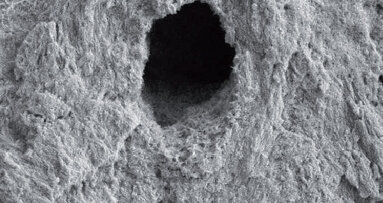

8) Dosažení optimálního hlavního apikálního průměru. Dosažení správného apikálního průměru koreluje se zvýšenou čistotou v endodontické literatuře. Tak velké apikální průměry zajistí jednak lepší proud irigačního roztoku a také lepší odstranění nekrotického dentinu. Je běžným zjištěním v případech, kdy endodoncie selhala, že apikální průměr i apikální konus jsou příliš malé.

Jednou cestou, jak definovat ideální hlavní apikální průměr je kalibrace. Jinak, lékař může jednoduše opracovat kanálek do požadovaného apikálního průměru, musí mít na paměti, že devitalizované zuby mají vyšší procento selhání ve velkých rozměrech, protože jsou obtížněji čistitelné ve srovnání s vitálními zuby (kde klademe důraz na asepsi spíše než na dezinfekci již infikovaného kanálku).